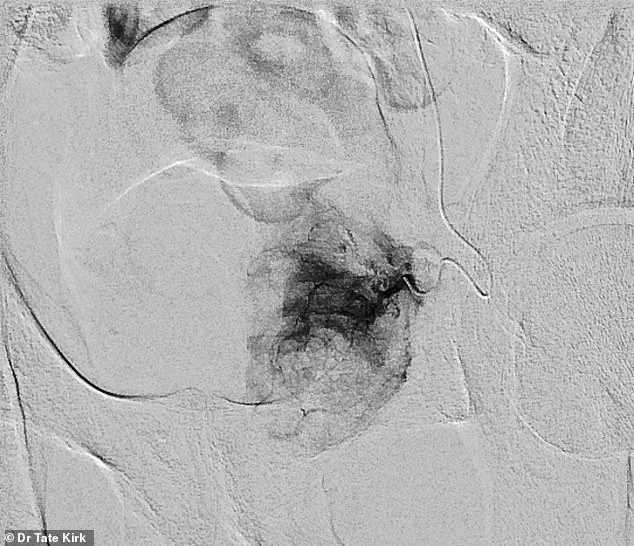

PAE works by targeting the blood vessels that supply the prostate.

A doctor begins by making a small puncture in the groin or wrist, through which a catheter is guided into the arteries feeding the prostate.

Using live X-ray imaging, the physician precisely navigates the catheter to the prostatic artery and injects tiny particles to block blood flow.

Over time, the reduced blood supply causes the prostate to shrink, alleviating pressure on the urethra and improving urinary symptoms.

The procedure involves inserting a catheter into the artery that supplies blood to the prostate, then using tiny particles to block blood flow to the overgrown tissue.

This targeted approach not only shrinks the prostate but also preserves surrounding structures, reducing the risk of complications that have long plagued conventional treatments.